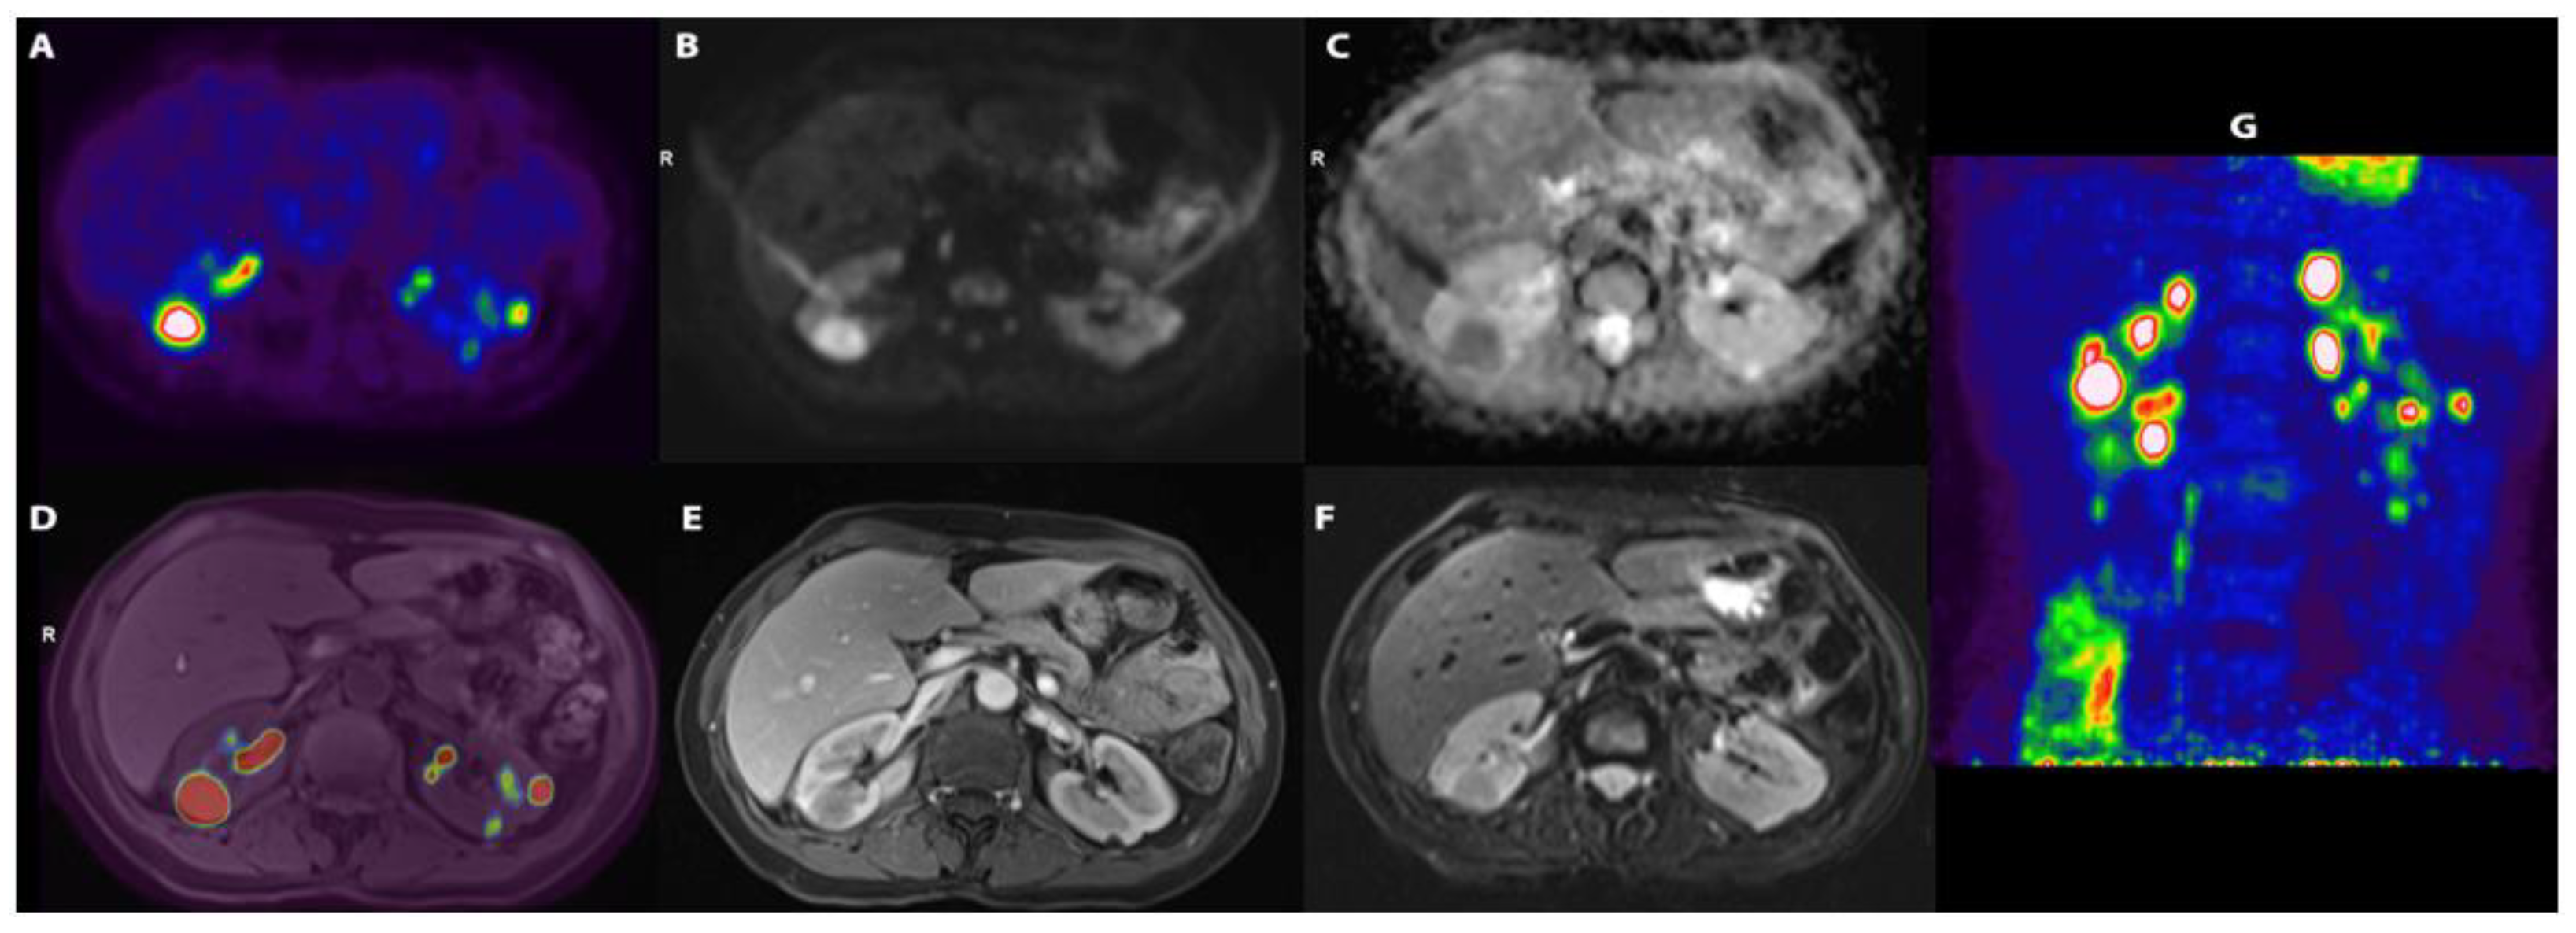

3.1. Personal Case Report

| Present case | F/49 | - | PR3 | Normal | US, CECT, PET-MR | Bilateral | Yes | No | Granuloma | RTX | Remission |